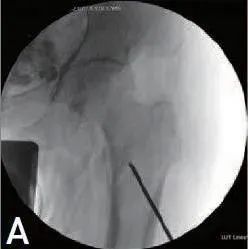

将 2.8 或 2.4mm克氏针引入 C 型臂前后 (AP) 视图上小转子水平的骨折间隙之间(图1A、B),在克氏针入口点处作一个切口。如果近端骨折块位于远端骨折块的髓内空间中,可以使用骨折牵引系统牵引和外旋受伤腿,插入克氏针,即可操纵并固定骨折间隙。通过骨折间隙插入克氏针后,用锤子敲击股骨颈下皮质,将内侧距下方的克氏针向前推。

图1 A,B 80 岁女性患者 AO/OTA 31-A2 股骨转子间骨折的头颅髓内钉附加复位螺钉。2.8mm克氏针被引入骨折间隙之间,在AP/ 侧向透视图上看到的小转子水平。